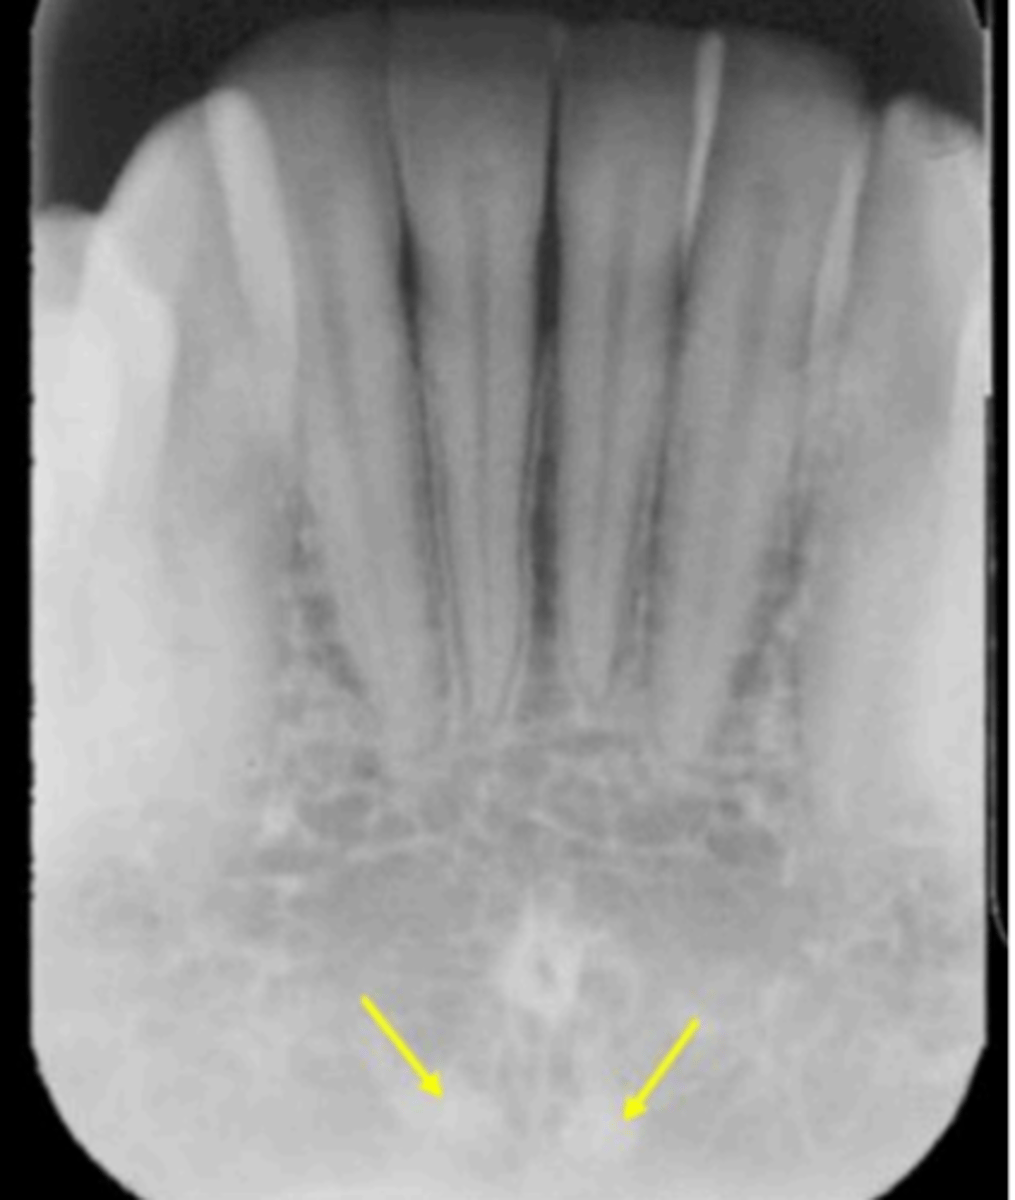

Intermaxillary suture (palatine suture)

Identify the structure

Incisive foramen

Nasopalatine canal

Superior foramina of the Nasopalatine canal

Superior foramina of the nasopalatine duct

Name the two round radiolucencies indicated.